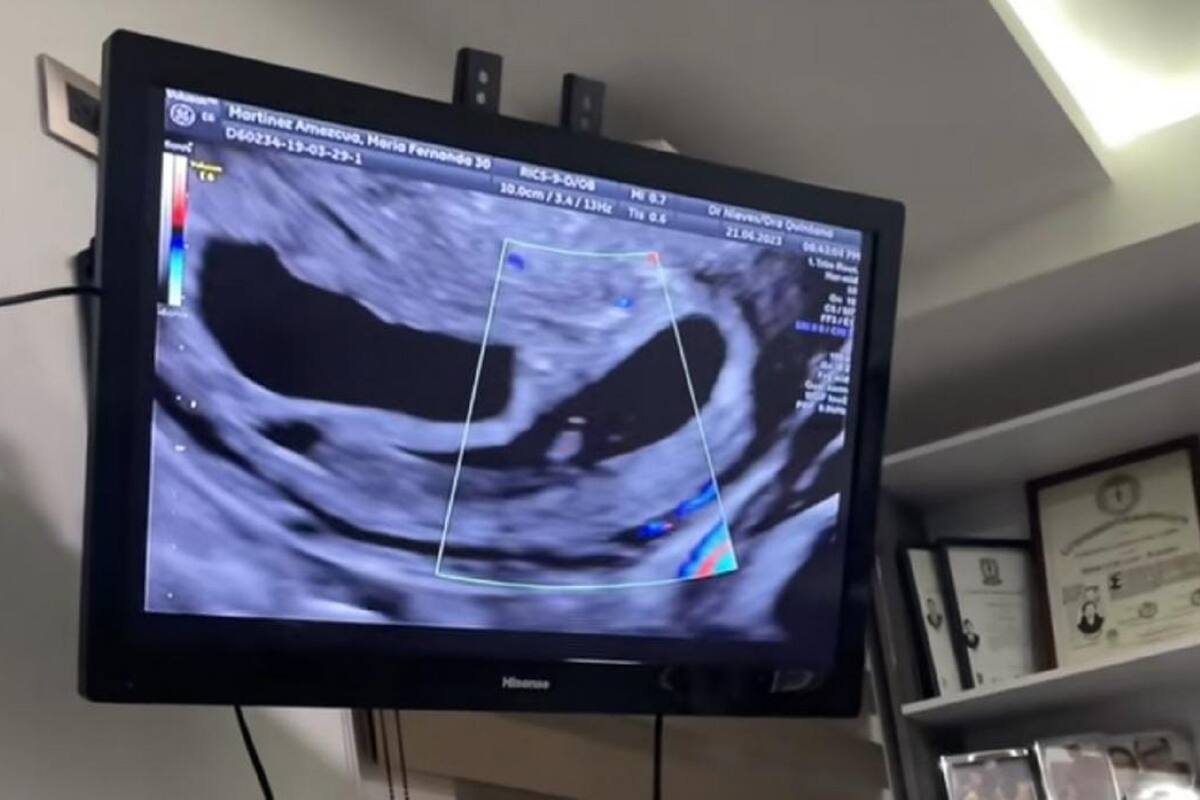

Posteriormente, se puede ver las diversas pruebas que le hace en la mujer a través de una pantalla, sin sospechar la noticia que están a punto de darle.

Finalmente, el doctor confirma a su paciente que se encuentra embarazada, y que además son dos, por lo que la mujer simplemente no lo puede creer.